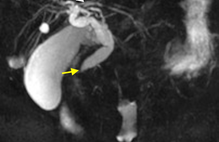

This 69-year-old woman received neoadjuvant docetaxel, trastuzumab, and pertuzumab with dramatic response and no untoward side effects. She then had a standard lumpectomy and lymph gland dissection followed by standard breast radiotherapy. Some weeks afterwards, she developed whole-breast allodynia with subsequent redness, swelling, and edema; marked reduction in shoulder mobility; and marked burning pain throughout the breast and axilla. There was no documented recurrence, and her pain persisted for a year, worsening to 10/10 worst pain and at best 6/10 deep aching pain. Treatment was given first to the breast, following the dermatomes across the breast, then to the axilla. After one treatment her allodynia was markedly better, as was the pain. She was retreated with several more treatments over the next months and is markedly better, back at work, able to wear normal clothes, and hasfull mobility of the shoulder and axilla (Figure 3).